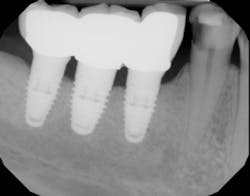

This technique should be used as standard practice when restoring caries adjacent to dental implants (figure 3).

Figure 3: Deep caries adjacent to dental implants is complicated by a deep sulcus. The two-matrix system margin-elevation technique is used to restore proper contour, emergence profile, and contact.